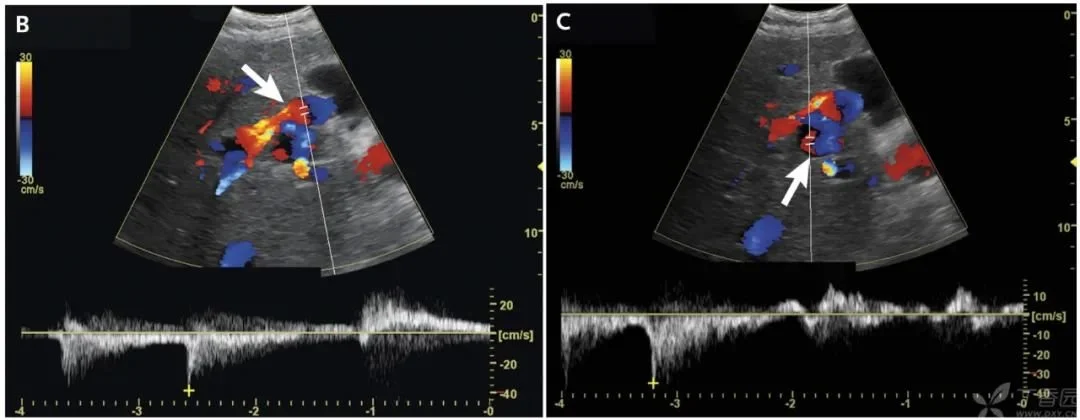

本次入院前一個月,患者因急性精神錯亂和水腫加重入院,并進行了右上腹超聲檢查,如下圖。

打開鳳凰新聞,查看更多高清圖片